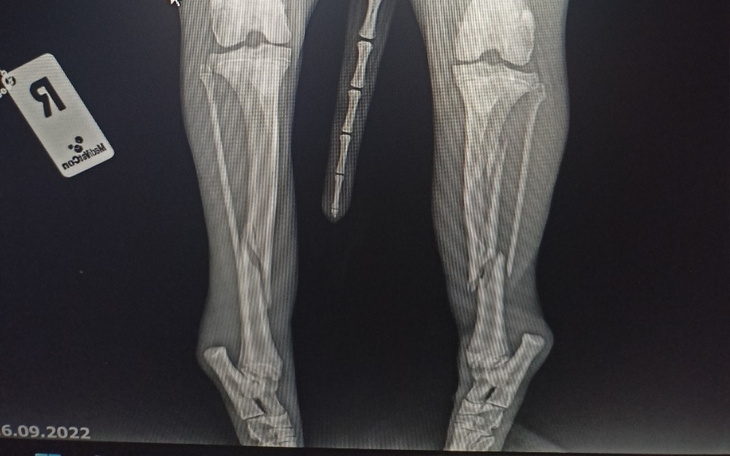

Cześć. Chciałbym bardzo prosić o pomoc w zbiórce pieniężnej na mojego pieska Roko. Pies dnia 13.09 został dosłownie najechany przez auto, które ruszało. Piesek był aktywny z nami w lesie, biega za zwierzyna, itp widocznie zmęczony schował się pod autem które ruszyło... Pies cudem uszedł z życiem. Roko ma całkowicie połamane kości, ma również złamane tylne łapki z przemieszczeniem.

Pies bardzo cierpi z bólu, ma dyskomfort z powodu załatwiania potrzeb fizjologicznych pod siebie, a termin operacji, nie jest jeszcze przewidziany, cały czas jeździmy do weterynarza. Nie wyobrażam sobie ile on znosi cierpienia oczekując na operacje w takim stanie przez tyle dni. Mieliśmy dużo szczęścia, ze życie Roko jest na ten moment ustabilizowane, ale by dalej funkcjonował wymaga kosztownej operacji, która wyniesie +/-6 tysięcy złoty, dodatkowo : leki, opatrunki, wizyty kontrolne, szpital całodobowy, rehabilitacja. Lekarz weterynarii zapewnia, ze operacja pomoże i pies będzie mógł chodzić. Wiek działa mocno na jego korzyść, ponieważ Roko ma dopiero niecały roczek, tak naprawdę to jeszcze szczeniak i ma całe życie przed sobą.

Oczywiście po pierwszym dniu w klinice weterynaryjnej zapłaciliśmy 500 zł, następnie musieliśmy zawieźć go do kliniki całodobowej, w której sam koszt pobytu wynosi 100 zł/ doba + koszt leków. Łączna wycena leczenia Roko wynosi ok. 10 000 tysięcy złoty. Niestety nie stać nas, by wydać tyle na leczenie, dlatego bardzo prosimy o wsparcie. Sam nie raz wpłacałem na rożne zbiórki na zwierzaki, a teraz sam znalazłem się w ogromnej potrzebie. Przesyłam dokumentacje od weterynarza oraz zdjęcia Rokiego z teraz i z dni w których był pełen życia. 😢

Dziękujemy za każdą, pomoc za każdą wpłatę, udostępnienie, Roko jest już po pierwszej operacji jednej nóżki ;( Zbieramy fundusze na drugą.